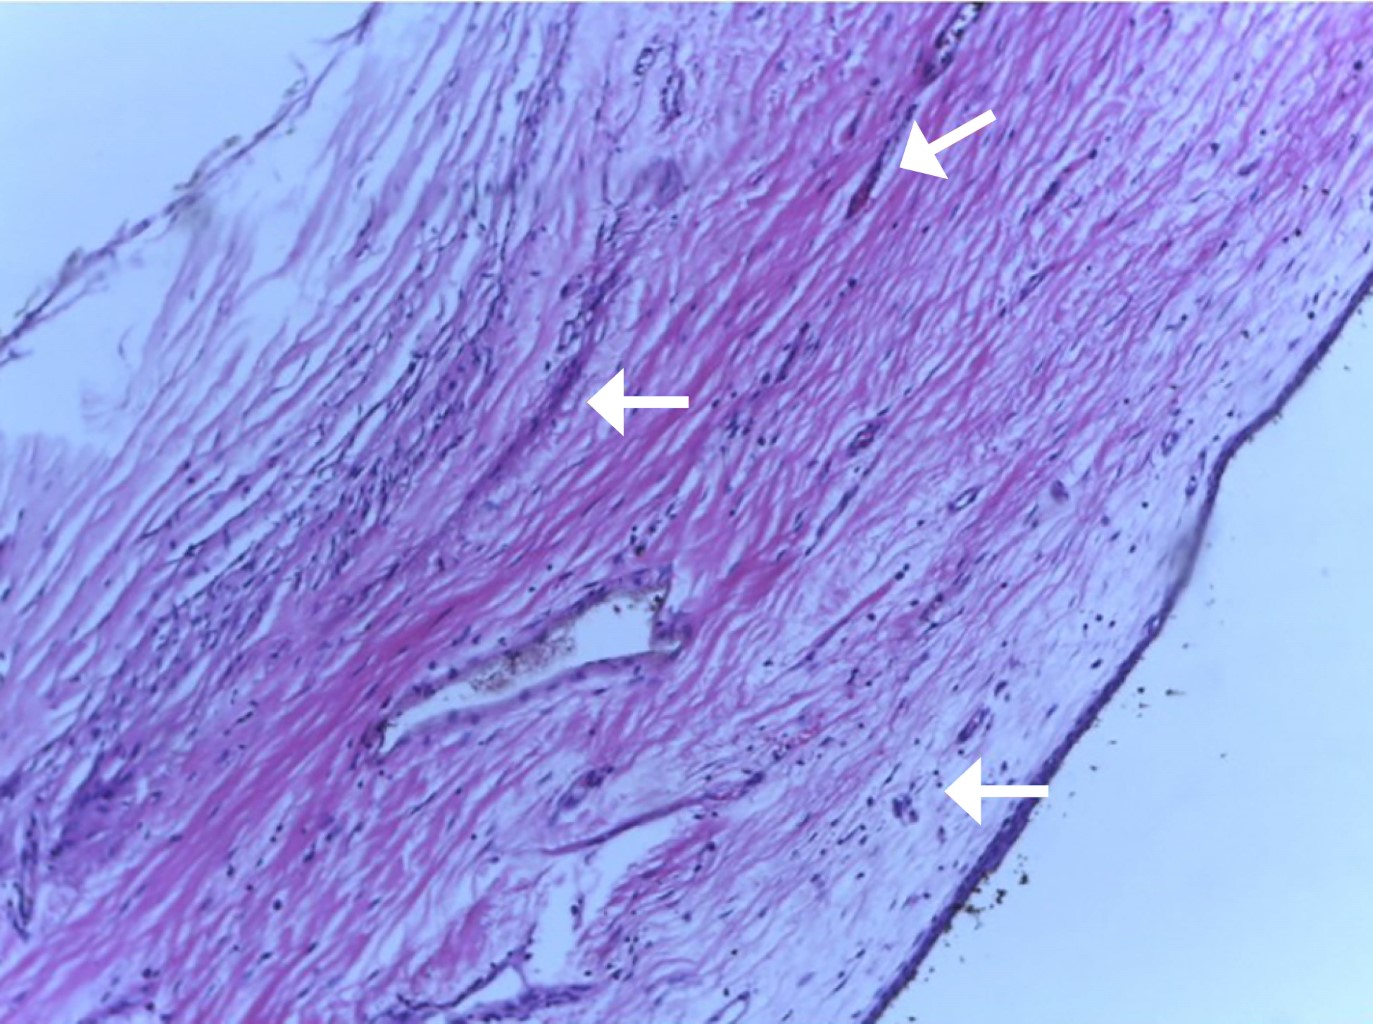

En el reporte del estudio histopatológico se describe de la siguiente manera: tumor de ovario izquierdo, mide 4.8 × 4 × 2.3 cm, de forma ovoide, con aspecto quístico, cápsula íntegra, superficie externa lisa, transparente, de color blanco grisáceo. Al corte, se encuentra lleno de líquido transparente, la superficie de la cavidad tumoral es lisa, color blanco, la pared mide menos de 1 mm de espesor, la consistencia del tejido es suave (Figuras 3 y 4). A la revisión microscópica, con tinción de hematoxilina/eosina se observó pared de tumor quístico formada por corteza de ovario, zona de hemorragia, presencia de macrófagos con pigmento compatible con hemosiderina y células gigantes tipo cuerpo extraño (Figura 5). La cara interna del quiste formada por epitelio cúbico simple sin atipias (Figura 6). Con todo lo anterior, se integró el diagnóstico de cistoadenoma congénito.

Figura 5